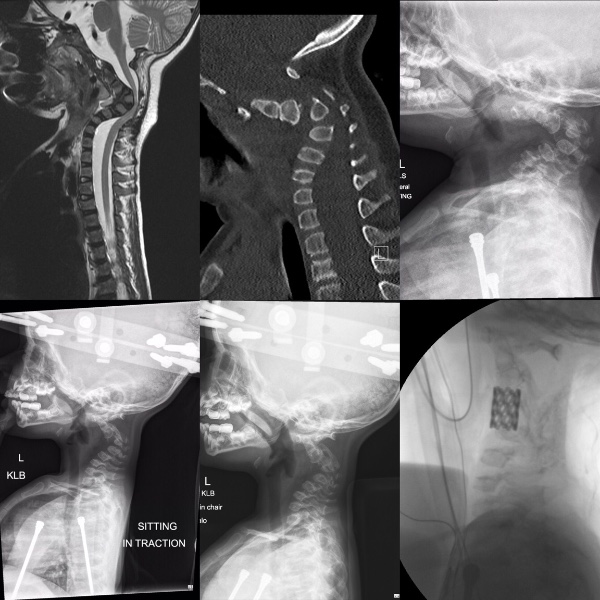

▼Chelsea與丈夫Curtis大吃一驚,醫生也被嚇了一跳。詳細檢查後他們才知道,寶寶的腿部發育比一般同期的胎兒整整晚了6週,她的骨頭很脆弱,患有先天性「成骨不全症」,也就是人們說的「玻璃娃娃」。

▼醫生為Zoe做了詳細的檢查,發現她罹患的是III 型而不是 II 型成骨不全症。她的症狀雖然也很嚴重,但情況比較輕微。在醫院待了一週後,Chelsea與Curtis終於帶著寶寶回家了。